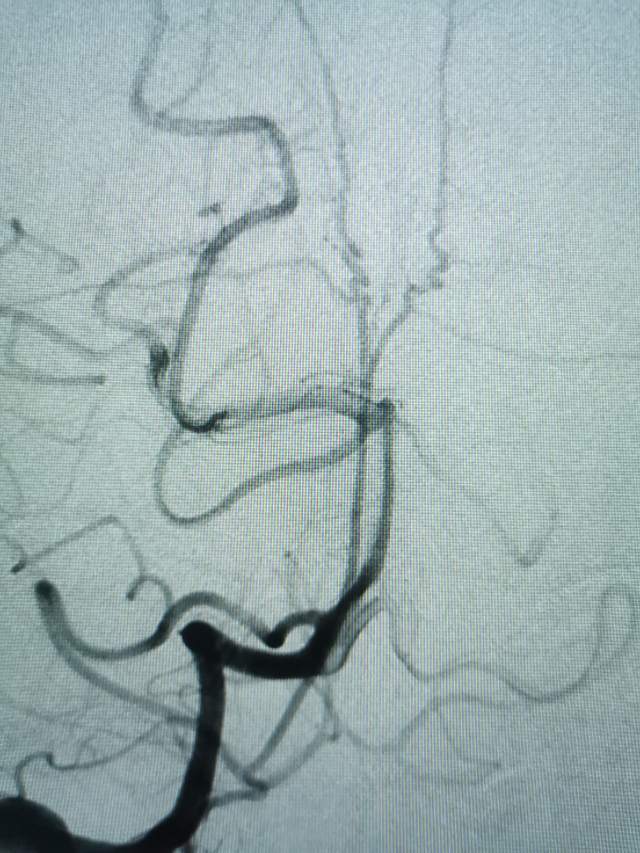

急诊绿色通道给予责任动脉瘤栓塞,远端破裂小泡完全不显影,近端瘤颈处小泡也基本不显影,胚胎性大脑后动脉保留良好。